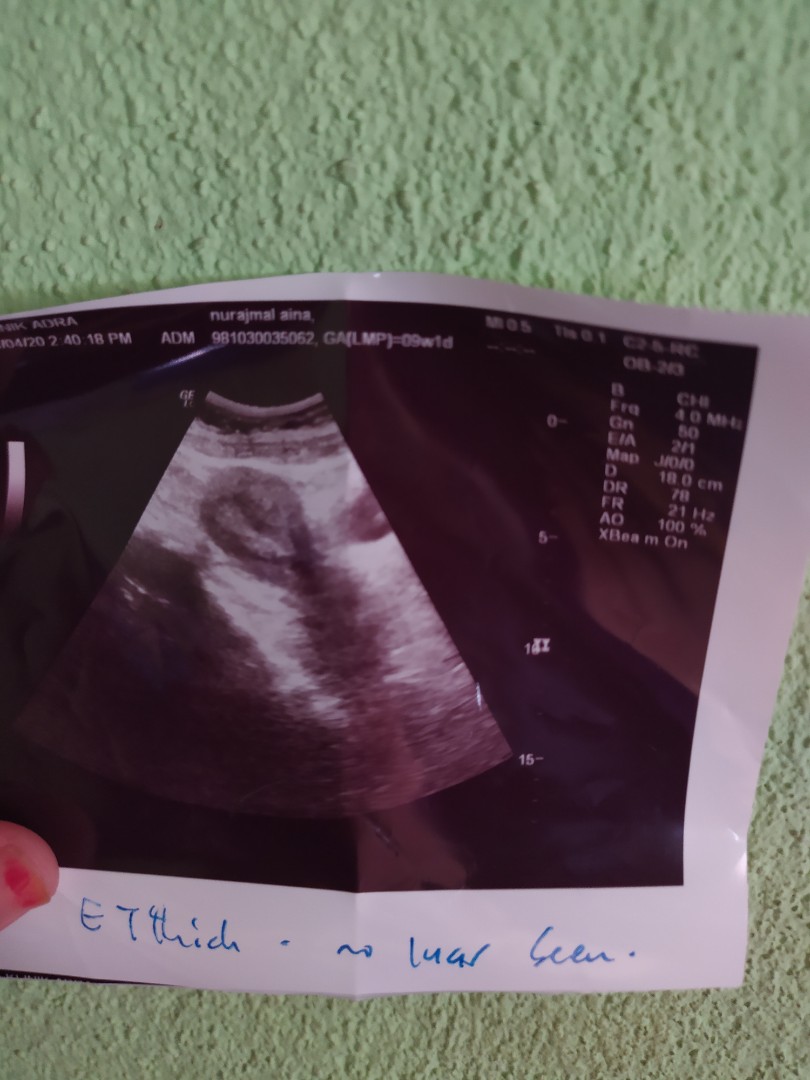

Salam mommies ada pengalaman tak scan masa 6 weeks hanya nampak kantung je. Normal ke?

Kalu ikut period 9week . tp kandungan sy mcm 6week